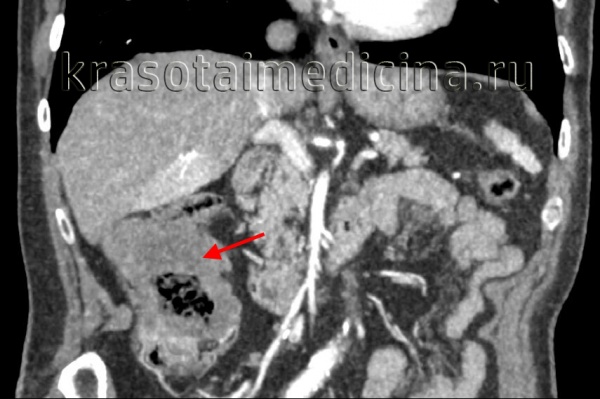

КТ ОБП/ЗП. Циркулярная мягкотканная опухоль (красная стрелка) стенки поперечной ободочной кишки, значительно суживающая ее просвет.